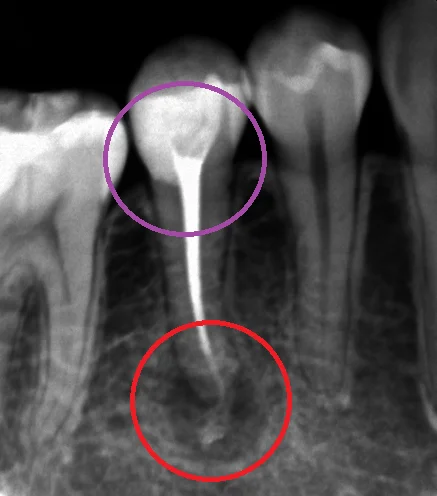

ちなみに、こちらが術前のレントゲンです。

保険内の白い詰め物のコンポジットレジンを行っているようですが、全く合っておらず、中で虫歯が大きくなっています。(紫の〇の所)

そしてそれが神経に達して、根の先に膿が溜まっています。(赤の丸の所)